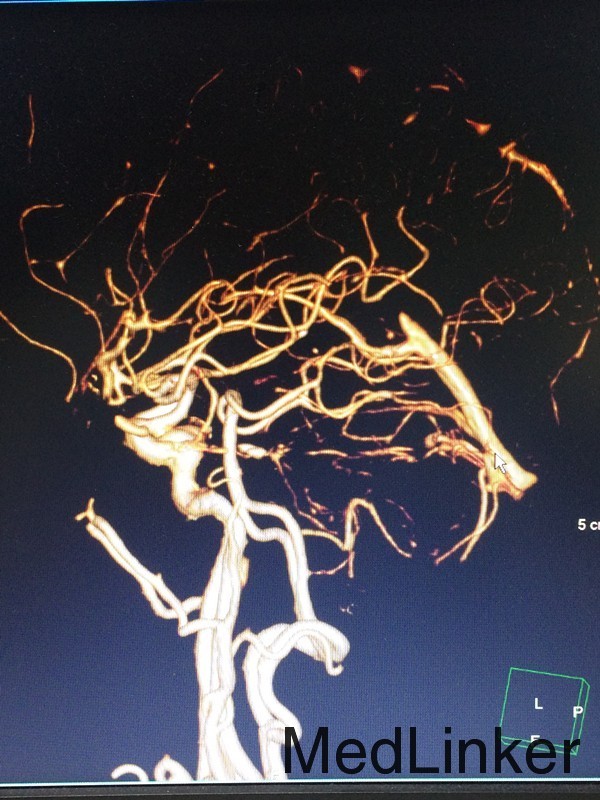

查体:左侧上肢2级,下肢2级,右侧肢体肌力正常 辅助检查:查头颅CTA提示:右侧额叶及岛叶(包括基底节)脑梗塞,轻度脑萎缩,CTA未见明显异常

随访:患者病情缓解出院 讨论:患者60岁男性,突发大面积脑梗塞,可能是由脑动脉主干阻塞所致,CT呈现大片状低密度阴影,多为脑叶或跨脑叶分布,脑组织损害范围较大,临床上除表现脑梗塞的一般症状外,还伴有意识障碍及颅内压增高。不排除为体循环的血栓掉落至大脑动脉引起。